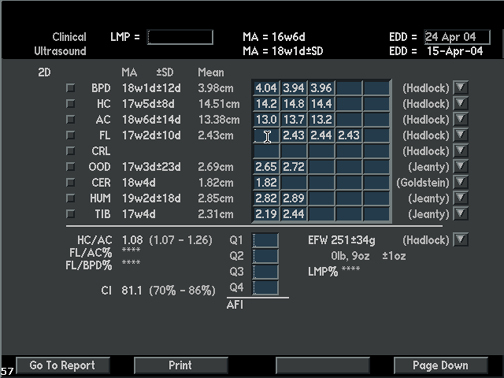

Items Measured by Ultrasound |

Measurements |

Measurement Graph |